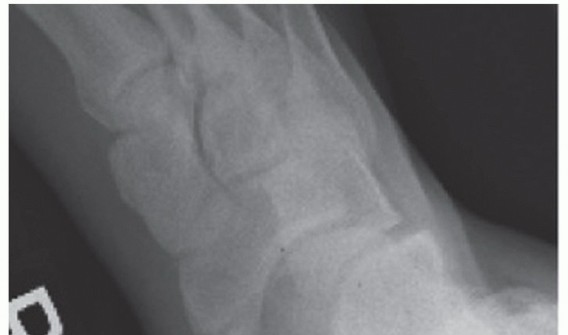

DEFINITION Arthritis of the ankle can evolve from multiple causes, including, but not limited to, osteoarthri…

DEFINITION The procedure to fuse the tibiotalar joint for isolated endstage tibiotalar arthrosis ANATOMY Ankl…

DEFINITION Arthroscopy of the ankle has become an invaluable tool for evaluating and treating pathology in th…

DEFINITION There are several reasons for cartilaginous defects of the ankle: Traumatic injury Osteochondritis…